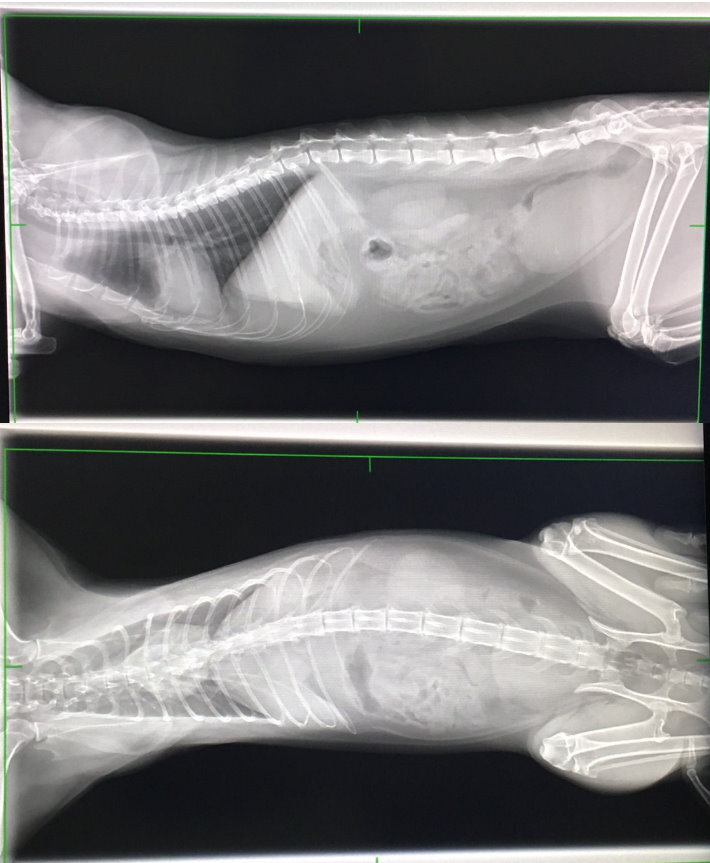

照X光檢查,排除異物阻塞的可能,

卻發現腸道無食物,表示多日未進食

X光中有看到心包膜有些微積水狀況

並於膀胱上發現有一白點,

但做超音波時並未看到結石等異物,

故推測是腸子的疊影。

超音波檢查到胰臟腫脹